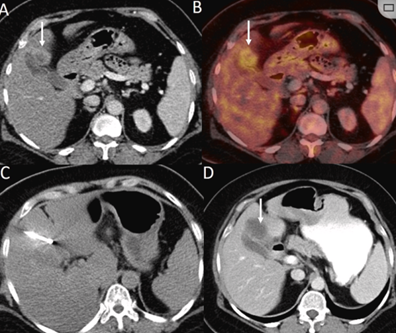

79 歲男性,肝轉(zhuǎn)移(結(jié)直腸癌)腫瘤的完全消融病例

( a ) 軸向 MRI 和 ( b ) 軸向 CT 顯示肝S8段有一個16mm的病灶,鄰近肝緣。( c )冷凍消融期間CT顯示放置了2個冷凍探針,低密度冰球包圍病灶。(d)術(shù)后1個月隨訪 CT顯示冰球?qū)?yīng)的壞死區(qū)域,未見復(fù)發(fā)。(e)術(shù)后6個月的CT,壞死區(qū)域縮小,未見復(fù)發(fā)。(f)與基線影像(g)相比,12個月后的FDG-PET/CT顯示未見FDG攝取。

62歲女性,肝轉(zhuǎn)移(卵巢癌)腫瘤的完全消融病例(a)軸向CT顯示病變位置毗鄰心臟和上腔靜脈(黑色箭頭)。(b)術(shù)中軸向CT掃描:使用三個冷凍探針。1個月后的軸向(e)和冠狀位(f)增強CT掃描顯示低密度區(qū)域,由于肉芽組織反應(yīng)引起的邊緣增強。

技術(shù)成功100%,92% 的病灶中觀察到腫瘤完全消融。16 名患者 (33%) 出現(xiàn)局部復(fù)發(fā)。10 名患者 (20%) 因局部復(fù)發(fā)或腫瘤消融不完全而接受二次冷凍消融術(shù)。

7名患者出現(xiàn)輕微并發(fā)癥,未發(fā)現(xiàn)膿腫形成、膽漏、膽汁瘤或血液學(xué)變化。冷凍消融可安全、有效治療毗鄰重要臟器的原發(fā)性肝臟腫瘤和肝轉(zhuǎn)移瘤患者,有效控制腫瘤局部進展,使患者生存獲益。我國作為肝癌大國,對于肝癌的治療一直給予高度重視?;趯<夜沧R和相關(guān)文獻(xiàn)研究結(jié)果顯示,冷凍消融技術(shù)具有高效、低成本、創(chuàng)傷小、適應(yīng)證廣、并發(fā)癥相對較少等優(yōu)點,可有效延長患者生存期、提高生活質(zhì)量、降低患者經(jīng)濟負(fù)擔(dān)。因此,冷凍消融技術(shù)在肝癌的應(yīng)用中有著極高的潛力和廣泛的發(fā)展空間。